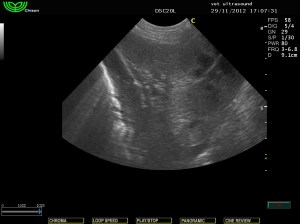

Στην υπερηχοτομογραφική εξέταση της κοιλίας βρέθηκε αύξηση της ηχογένειας της φλοιώδους μοίρας των νεφρών.

(ίδια ηχογένεια με το παρέγχυμα του σπλήνα)